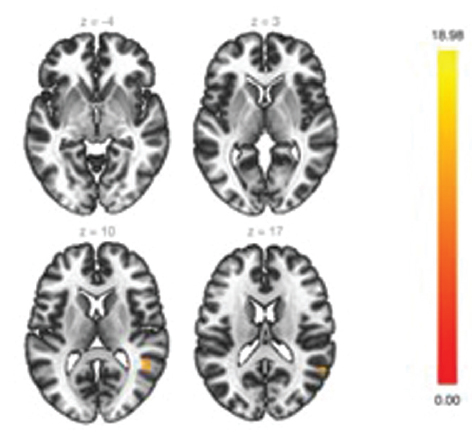

При оценке кластера № 2 (рис. 2) было выявлено увеличение активности в области язычной извилины. Данные изменения также вносят вклад в улучшение результатов клинических тестирований, а главное, в качество жизни пациентов. Увеличение в области обнаруженного кластера демонстрирует высокий потенциал к восстановлению основной нейросети покоя головного мозга, т. к. часть клеток этой области связана с медиальной префронтальной корой. Эти изменения помогают заподозрить причину положительного изменения настроения пациентов, уровня когнитивных способностей, некоторых двигательных функций.

Рис. 2. Кластер № 2 сети пассивного режима

Fig. 2. Cluster N 2 of the default mode network

Если говорить о функциональной принадлежности обнаруженных кластеров, то участки 2 и 3 кластера (рис. 2, 3), ассоциированных с сетью пассивного режима (СПР), лежат в областях, расположенных близко к структурам, участвующим в образовании данной нейросети, что свидетельствует о восстановлении функциональной коннективности самой нейросети. И на основе этого феномена потенциально можно ожидать улучшения результатов тестирований памяти, внимания, психологической составляющей, снижается выраженность двигательной дисфункции за счет улучшения функции планирования действий, повышается качество жизни.

Рис. 3. Кластер № 3 сети пассивного режима

Fig. 3. Cluster N 3 of the default mode network

Полученные нами данные о том, что в группе пациентов, которые находятся в ремиссии больше года после терапии, есть увеличение функциональной коннективности данной нейросети, свидетельствуют о появлении репаративного потенциала, возможно, на основе нейропластичности или нейроногенеза.